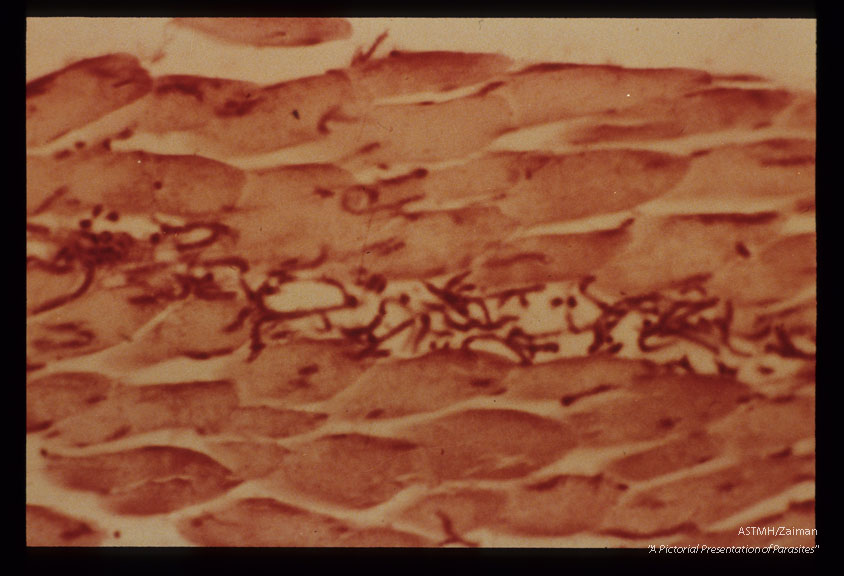

H & E stained section of muscle injected 10 minutes earlier with newborn larvae.

Trichinella spiralis

Description: H & E stained section of muscle injected 10 minutes earlier with newborn larvae.